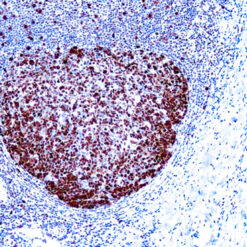

The Warthin-Starry Stain Kit is intended for use in the visualization of Spirochetes, Helicobacter pylori, Legionella pneumophila, and Cat Scratch Fever bacteria. This kit may be used on formalin-fixed, paraffin-embedded sections.